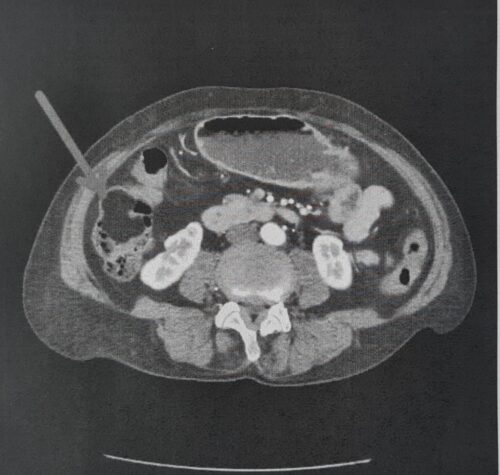

I suoi quattro figli hanno dato il consenso alla donazione senza esitazione: una donna di 82 anni di Canosa ha donato il fegato prelevato dalla equipe del Policlinico di Bari….